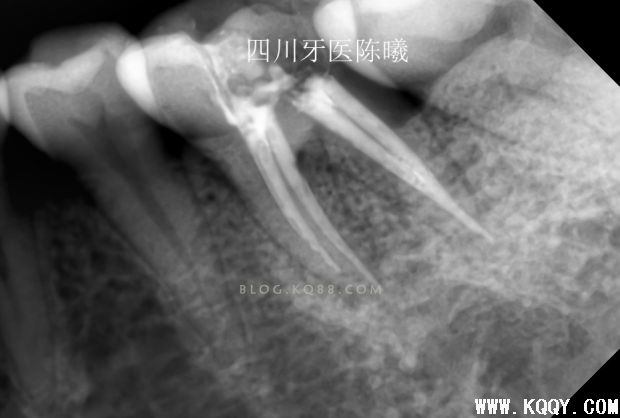

可以看出在取出近远中颊根充填物后,远中依然超填,说明远中超填的是舌根,然后觉得近中舌根充填锥度也不连续,干脆全部取出重新做!

这次留个后路,把刚才超填的牙胶去掉头部1MM,然后保留大部分牙胶,紧密充填后拍片!,终于感觉及格了,还是多角度看看